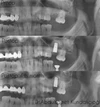

Mezun olduğu yıl İstanbul Üniversitesi Diş Hekimliği Fakültesi Ağız, Diş ve Çene Cerrahisi Anabilim Dalı’nda doktora eğitimine kabul edilmiştir. 2018 yılında ‘Ön Açık Kapanış Olgularında Uygulanan Le Fort I Osteotomisinin Stabilizasyonunun Farklı Plak Tasarımına ve Ameliyat tekniklerine Göre Sonlu Eleman Analiz Yöntemiyle İncelenmesi’ konulu tezini sunarak doktorasını tamamlamış ve ‘Bilim Doktoru’ ünvanı almıştır.